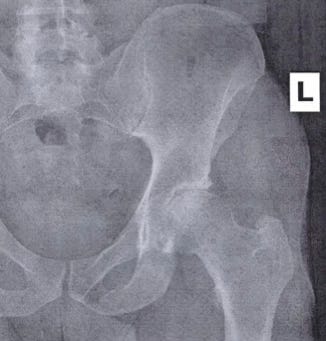

So I did what I should have done much sooner and saw the orthopedist my wife had seen about her hip. And I learned I have severe osteoarthritis. An MRI later confirmed that plus a torn labrum (anterior, posterior, and superior). And complete superior cartilage loss.